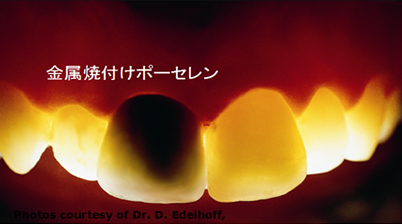

金属焼付けポーセレン(金属の上にポーセレンを焼付けたもの)

ジルコニア焼付けポーセレン(ジルコニアの上にポーセレンを焼付けたもの)